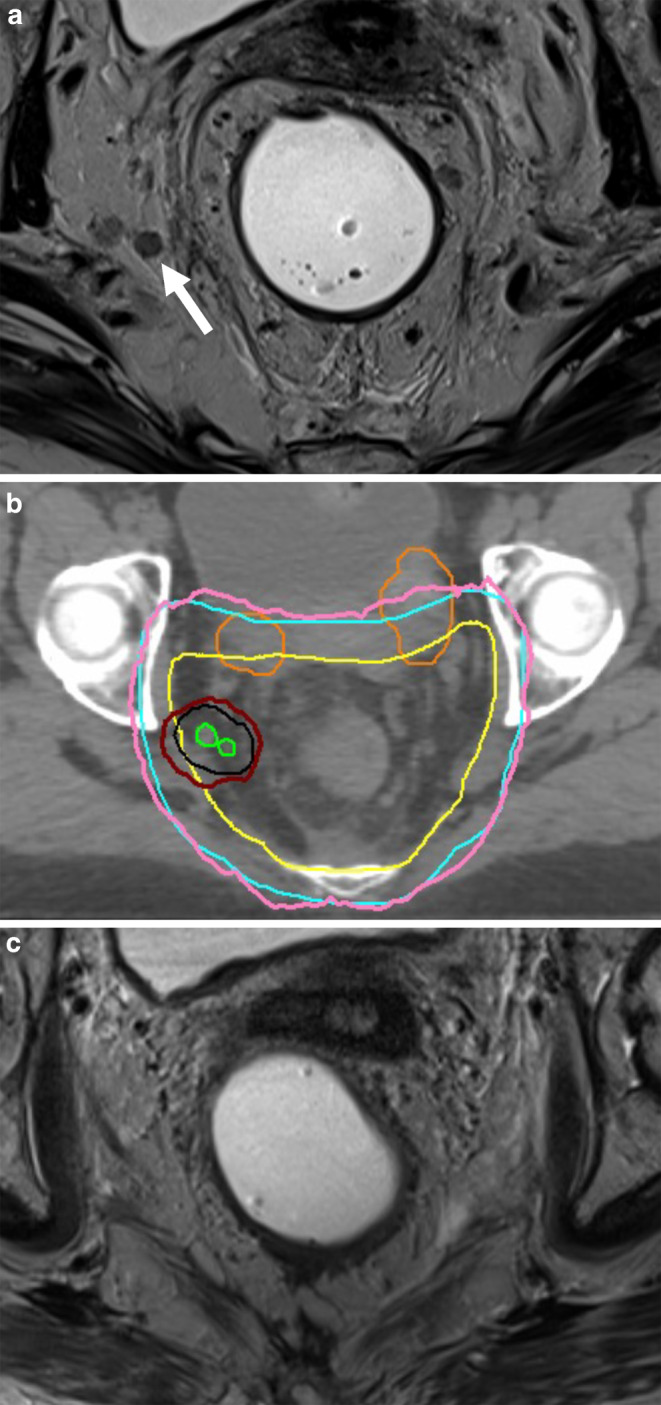

Background: Preoperative chemoradiotherapy combined with total mesorectal excision (TME) is a standard treatment for locally advanced rectal cancer (LARC). However, lateral pelvic lymph nodes (LPLNs) are often inadequately treated with standard regimens. This study examines the treatment and postoperative outcomes in LARC patients receiving a simultaneous integrated boost (SIB) for LPLNs during long-course chemoradiotherapy.

Methods: This retrospective study included high-risk LARC patients (UICC, "Union Internationale Contre le Cancer", stage III) treated with preoperative chemoradiotherapy and SIB to LPLNs. Radiotherapy was delivered to the primary tumor and elective volumes with 50.4 Gy in 28 fractions, and an SIB with a median dose of 60.2 Gy was administered to clinically positive LPLNs. TME quality and postoperative complications were assessed using MERCURY and Clavien-Dindo, respectively. Time-to-event data were analyzed according to Kaplan-Meier.

Results: Between 2019 and 2023, 27 patients with high-risk LARC and LPLN metastases were treated with chemoradiotherapy. After a median follow-up of 19 months, 2‑year overall survival was 80%, disease-free survival 80%, and local control of dose-escalated lymph nodes 100%. Three patients were managed nonoperatively after a clinical complete response on endoscopy and imaging. Of the 22 patients who had surgery, only one had complications higher than Clavien-Dindo grade I; TME was graded as MERCURY I in 73%.

Discussion and conclusion: The SIB approach for LPLNs in LARC is feasible, does not increase postoperative morbidity, and achieves excellent local control. This study supports the consideration of dose-escalated radiotherapy for LPLNs to address high local recurrence risks.